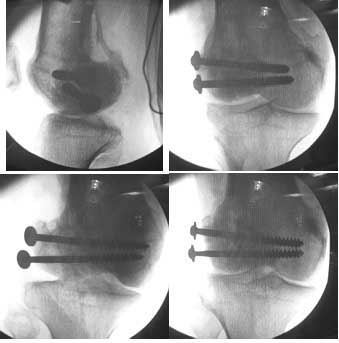

I opened it up from the lateral aspect.

Freed up the non-union site with minimal disturbance to the posterior and lateral soft tissue attachments on the lateral condyle fragment.

Applied a distractor between femoral shaft and tibia, to create a space on the lateral aspect.

This brought the lateral condylar fragment into a position that seemed to be reasonably well aligned, but showed up a bone gap.

This was fixed temporarily, bone grafted with tricortical struts, and fixed by two cancellous screws. The fragment was not large enough to afford any fixation to a plate or such implant, and the screws held it compressed well to the rest of the distal femur.

Post-op - limb is well aligned, rom 0-30, but I am not pushing that right now, for the next two or three weeks.

Further plan - hope that the screws hold the fragment appropriately till union, but if the stability on table is anything to judge by, that should not be a problem.

Quadricepsplasty after a year or so, to restore flexion.

Pictures attached.

Mangal Parihar